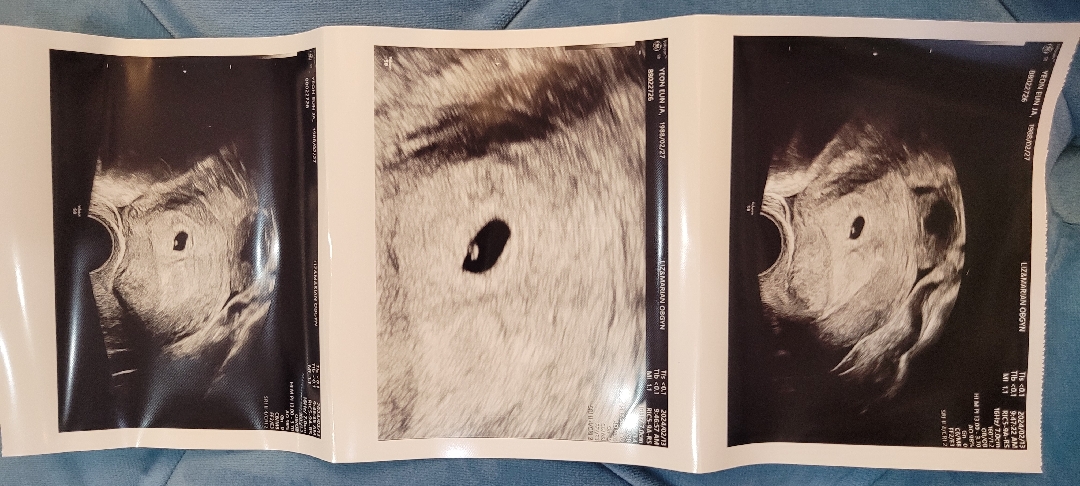

아기집이랑난황까지^^

오랜 기다림끝에 나에게도 이런행운이ㅜ 그동안 고생했고 앞으로꽃길만걷자♡